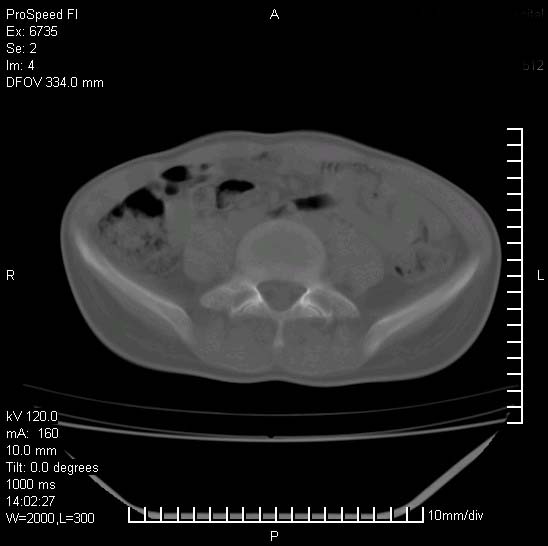

患者自诉胯部疼痛两年余,在当地服用中药,半月前至本院考虑骶髂关节结核,给予抗痨治疗。现发展至右下肢疼痛明显,活动受限,以膝关节处明显,拍膝关节平片无明显异常。

两侧骶骼关节改变,考虑强直性脊炎

左侧骶髂关节面限局性骨破坏,边缘硬化关节腔见钙化物;不出外tb

右侧骶髂关节也有类似改变,只是较左侧轻,首先考虑强直性脊柱炎,不除外结核,建议作hla-b27检查。

典型强脊炎改变,髋关节亦有累及

符合强直性脊柱炎表现。